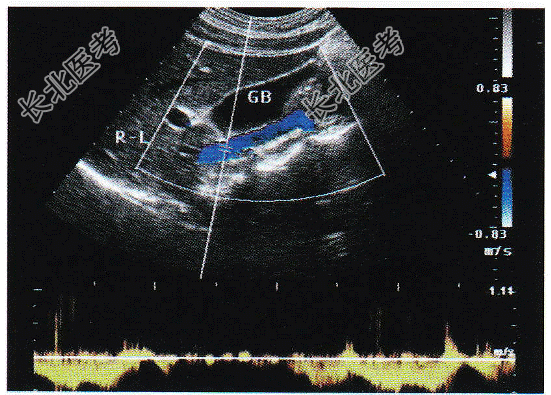

- 单项选择题请问下图箭头所指部位及彩图取样门宽所采及部位的解剖名称为:

A、门静脉

B、肝静脉

C、腹主动脉

D、下腔静脉

E、脾静脉